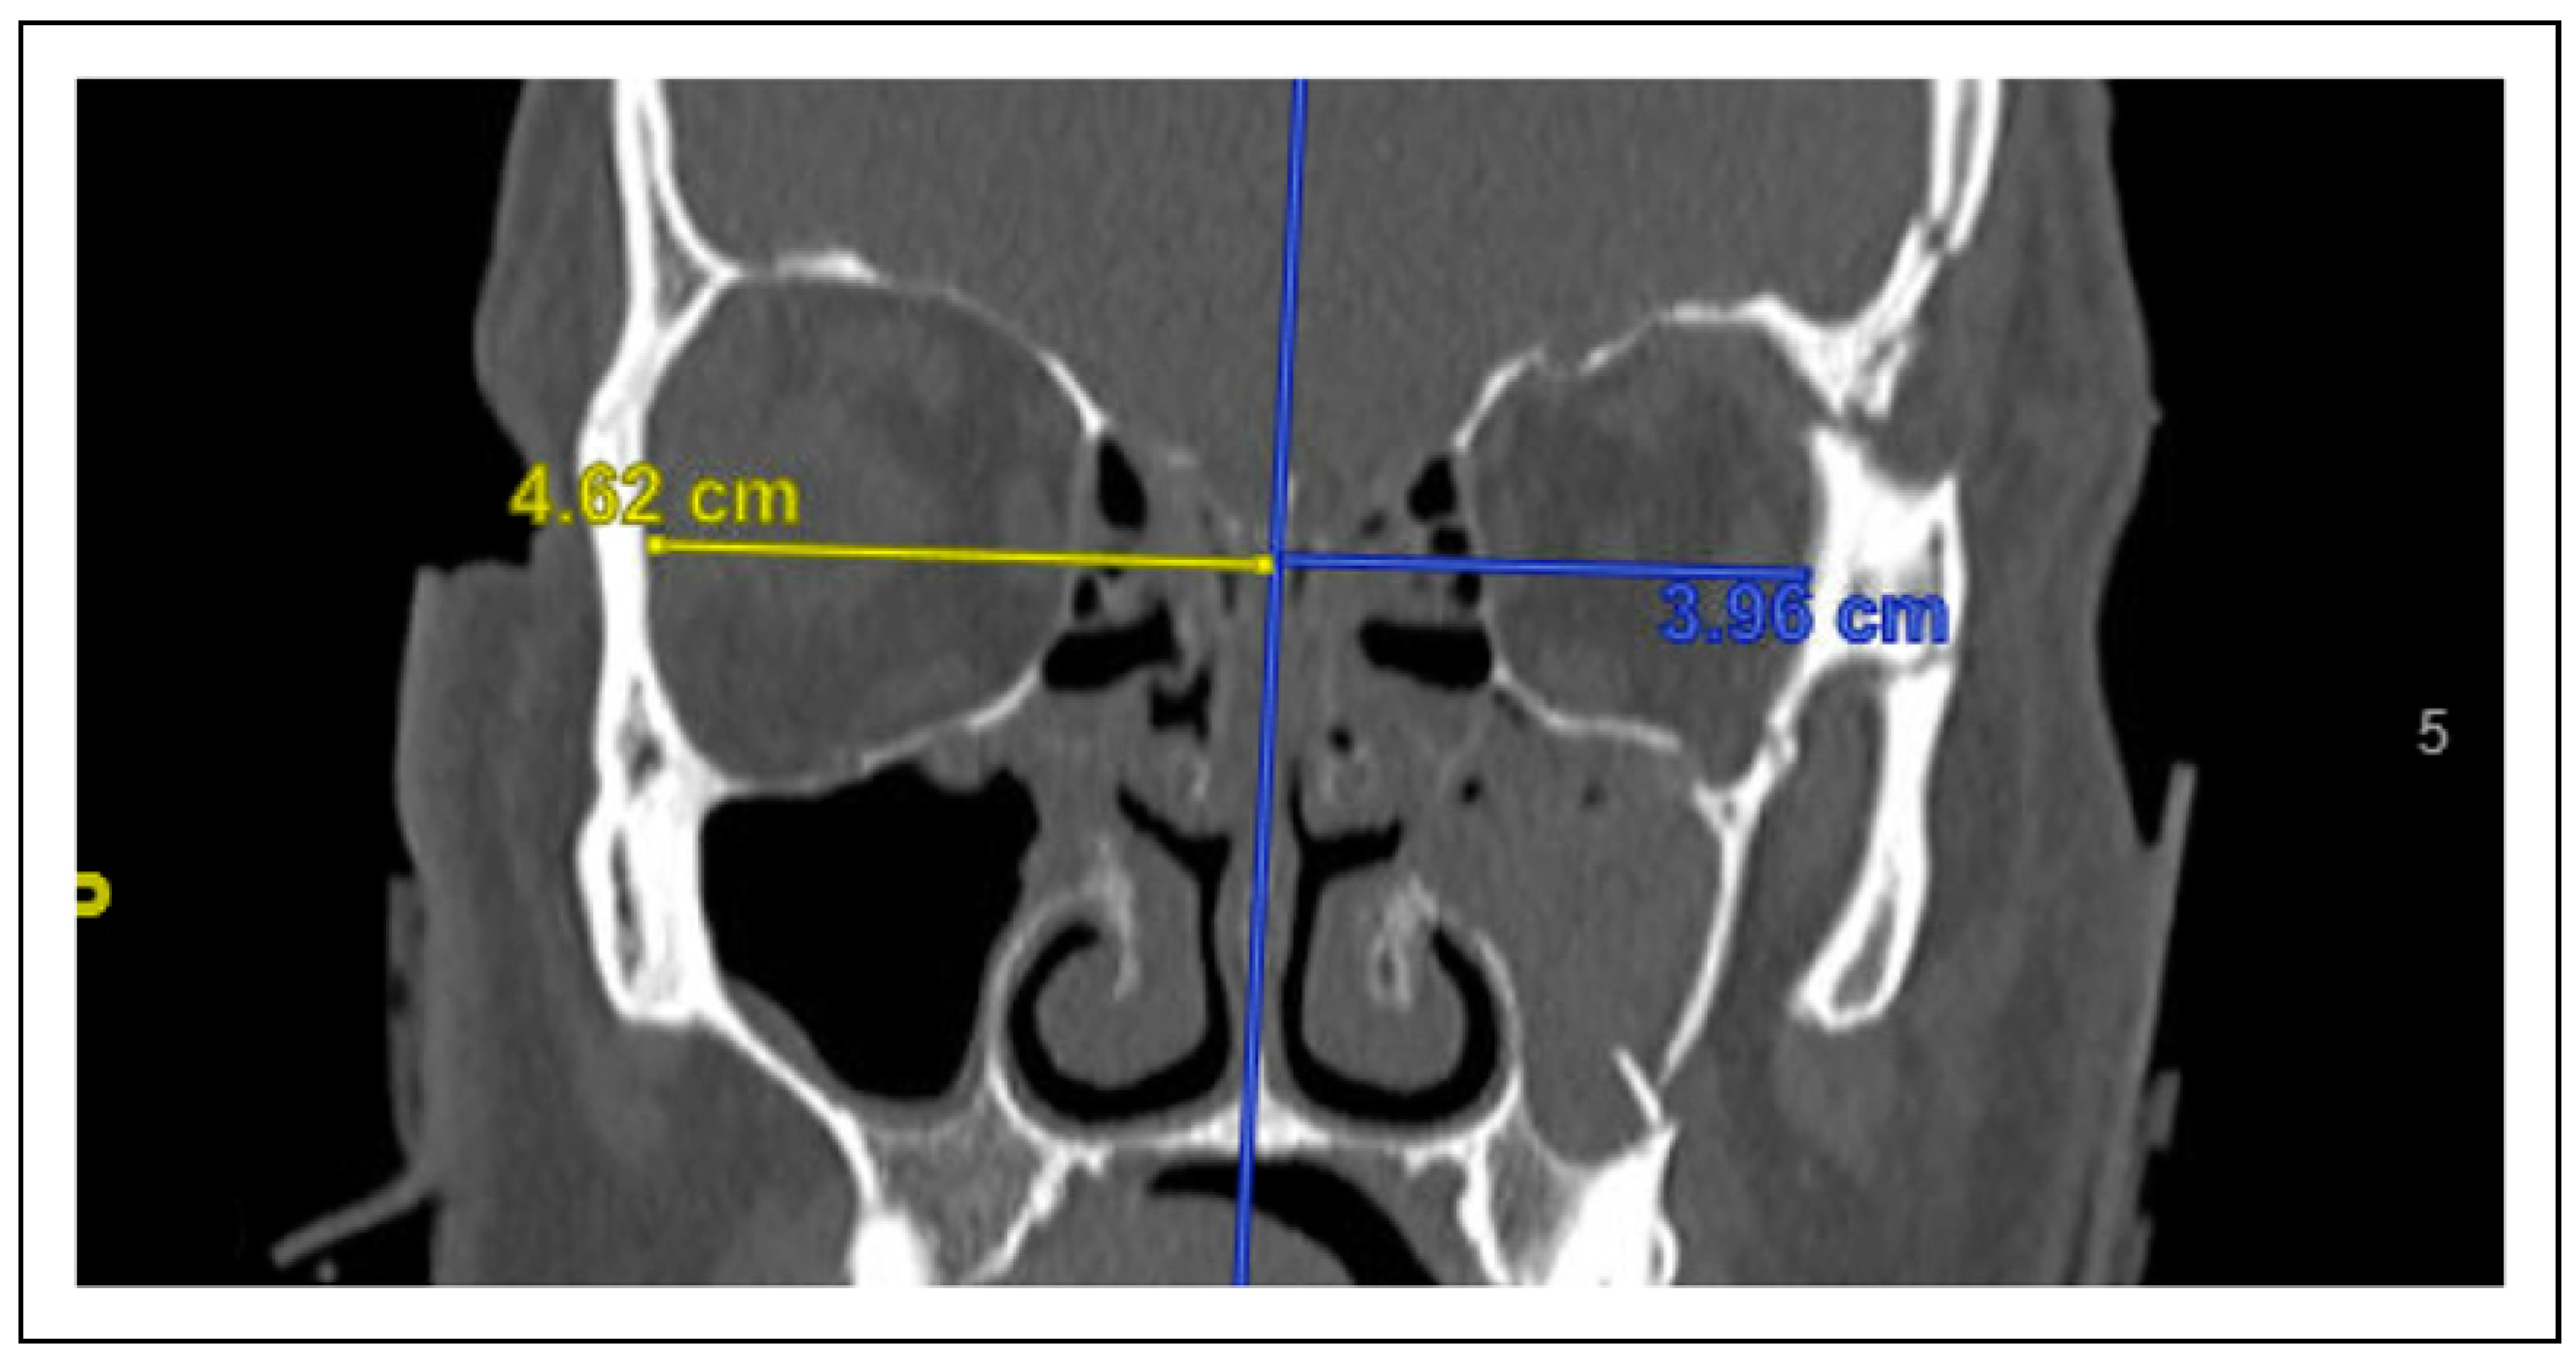

Figure 4. A photo of vertical displacement of the zygoma. This measurement was standardized using a horizontal reference line between the superior-most points of the supraorbital rim within the coronal plane. The distance between the inferior-most part of the infraorbital rim and a directly perpendicular point on the reference line was measured; vertical displacement was defined as the difference between these measurements of the injured and non-injured sides of the face.

Computed tomography imaging characteristics of the fractures at initial presentation were similarly documented. Data elements measured in this study were (1) medial displacement or impaction of the lateral wall of the maxillary sinus (Figure 1), (2) zygoma angle of rotation (Figure 2), (3) anterior-posterior (AP) displacement of the zygoma (Figure 3), (3) cranial-caudal or vertical displacement of the zygoma (Figure 4), and (4) lateral-medial displacement (LM) of the zygoma (Figure 5). For all vector measurements, the uninjured side served as an internal control.

Vertical Displacement

Vertical displacement on CT imaging significantly predicted the presence of malocclusion (OR = 1.47, P = .03). For every millimeter increase in vertical displacement, patients were 1.47 times more likely to experience malocclusion. Patients with subjective malocclusion exhibited an average of 1.3 mm of inferior displacement; meanwhile, patients without malocclusion exhibited an average of —.3 mm of inferior displacement, or .3 mm of superior displacement. Vertical displacement did not predict any other symptomatology addressed by this study.

When analyzing the various possible displacement vectors for patients with ZMC fractures, we found the critical vectors that significantly predicted clinical symptomatology were lateral maxillary wall impaction (Figure 1), AP displacement (Figure 3), and vertical displacement (Figure 4). LM displacement (Figure 5) did not demonstrate a statistically significant association with any of our collected clinical variables.

In contrast, vertical displacement of the zygoma did not affect malar position but did exhibit a statistically significant increased odds for subjective malocclusion (OR = 1.47, P = .03). Among our 95 patients with ZMC fractures, complaints of malocclusion were rare, occurring in only 10 patients. Patients noting malocclusion would complain of early contact or shifting of their teeth on the affected side. Previous literature have suggested that a sense of malocclusion following ZMC fractures is a result of either infra-orbital neuropraxia or soft tissue swelling and not necessarily related to displacement degree or vector [13,14]. Malocclusion in ZMC fractures may also result from masseter spasm secondary to facial trauma, which may pull the mandible toward the ipsilateral side and temporarily mimic the presence of a crossbite [15]. In our cohort, vertical displacement was the only vector statistically associated with malocclusion. There are 2 proposed mechanisms whereby vertical displacement could account for this: (1) inferior displacement of the zygoma may lead to increased compression of the infraorbital nerve as it exits the infraorbital foramen; (2) vertical shift of the zygoma may inferiorly displace the alveolus, potentially altering the position of the maxillary teeth. The findings of this study suggest that clinicians should be suspicious of skeletal malocclusion in the setting of vertical displacement in patients with ZMC fractures. In addition to describing clinically significant displacement vectors in patients with ZMC fractures, we hope to provide general guidelines when evaluating patients with ZMC fractures radiographically. In our study, we found that ZMC fractures with concomitant lateral maxillary impaction of > 4.5 mm were 12 times more likely to require surgery compared to patients with ZMC fractures with a lesser degree of displacement in this vector (P < .001). Additionally, patients with ZMC fractures that exhibited > 2.5 mm of posterior displacement in the AP vector demonstrated 14.3 times increased odds for surgery (P < .001) (Figure 6). Taken together, these 2 displacement vectors and measurement cut-offs place patients with ZMC fractures into an increased risk category for potential operative intervention, which should influence patient counseling, shared operative decision-making, and determine need for close follow-up. Outcomes assessment of surgical follow-up data, which indicate that surgery significantly benefits patients with injuries meeting these thresholds (Figure 10 and Figure 11), supports these radiographic cut-offs for operative intervention. Specifically, operating on these subsets of surgical candidates can be expected to yield significant improvement in symptoms including appreciable displacement or palpable step-off and malar changes—a finding that further validates the relationships between these symptoms and the radiographic characteristics LMWI and AP displacement noted earlier in this study (Table 4). Moreover, our findings may also guide decision-making regarding which patients do not need surgery. Unsurprisingly, plastic surgeons can feel confident that patients without any symptomatology may be managed conservatively (P < .001). In patients who do present with symptoms, surgeons can feel relatively confident that those without a clinical presentation of trismus, step-off of the infraorbital rim, or malar flattening may also be managed conservatively. Certain radiographic characteristics, including a maximal anterior-posterior displacement less than 3 mm or maximal vertical displacement less than 2 mm, were also consistent with a lower chance of requiring surgery (P < .001 and P = .02, respectively). Moreover, patients whose fractures are displaced less than 15 mm in all vectors may be counseled that their injuries are at very low risk for requiring surgical intervention (P < .001) (Figure 7). Together, these clinical presentations and displacement cut-offs place certain patients with ZMC fractures at lower risk for operative management and can, as a result, be used to systematically inform which patients do not require additional follow-up.